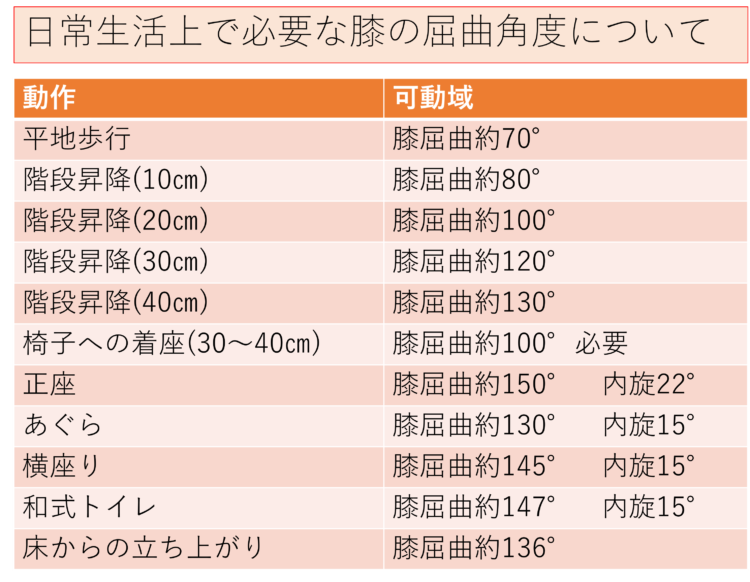

5. リハビリや運動に対するモチベーションを与える

リハビリ計画を遵守することが重要です。多くの人にとって、これは 1 日に 2 ~ 3 回 30 分間歩くことを意味します。医師は、1 日に 2 ~ 3 回、さらに 20 ~ 30 分間の運動を推奨することもあります。

歩いたり運動したりすると痛みを感じることがあります。これは正常です。患者がリハビリ計画を中止したいという意思を表明した場合は、彼らが感じていることはよくあること、リハビリが回復を早めるのに役立つことを思い出させてください。

膝関節全置換術の回復スケジュールについて詳しく知ることが役立ちます。